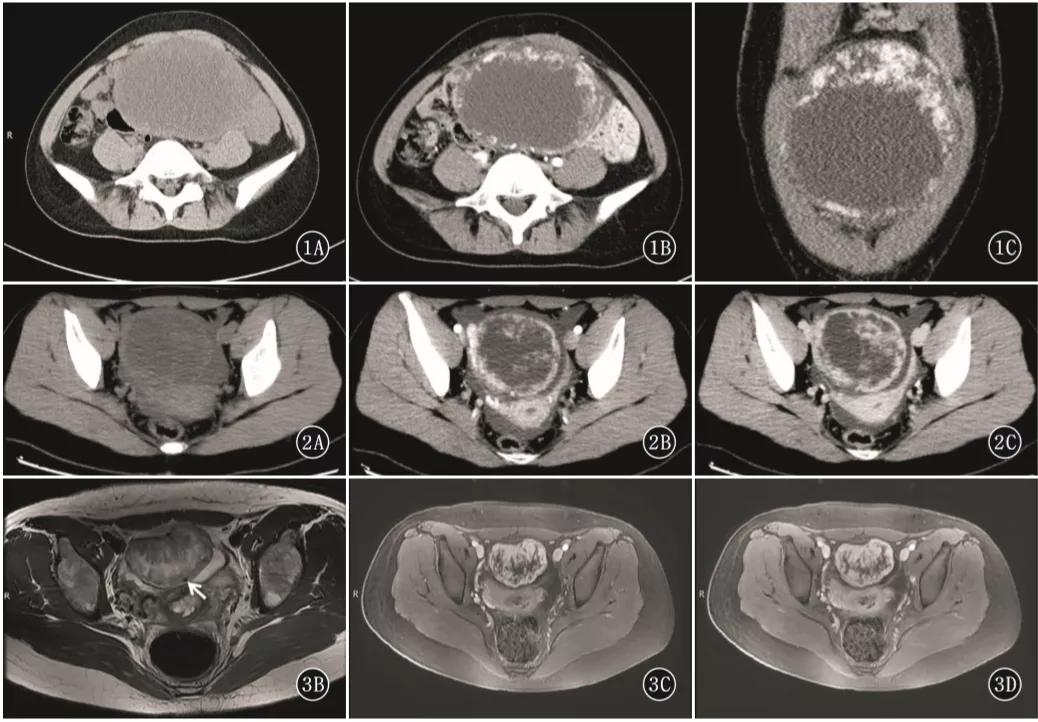

图 1. 女,22 岁,左侧卵巢硬化性间质瘤。CT 示左侧附件区囊实性巨大肿块,增强后肿瘤周边呈明显持续性强化,肿块周边多发结节及乳头状强化,中央囊性成分未见明显强化。

图 2. 女,42 岁,左侧卵巢硬化性间质瘤。盆腔内巨大囊实性肿块,平扫呈等密度,肿块内部及周边多发絮状及乳头状结节,增强后肿块呈持续性显著强化,向 心性推进,强化绒毛呈「梳齿样」强化。

图 3. 女,19 岁,左侧卵巢硬化性间质瘤。T2WI 轴位(图 3B)示盆腔内囊实性肿块,实性区域与囊变区相交错,呈「梳齿样」表现,肿块边缘见低信号包膜,实性成分呈结节及乳头状等信号,中央囊变区呈裂隙状稍高信号,低信号包膜下见流空血管影(箭头),增强扫描轴位(图 3CD)静脉期及延迟期盆腔内肿块周围实性成分呈显著持续性、向心性强化;中间裂隙状囊变区无强化,表现为「湖岛」征。